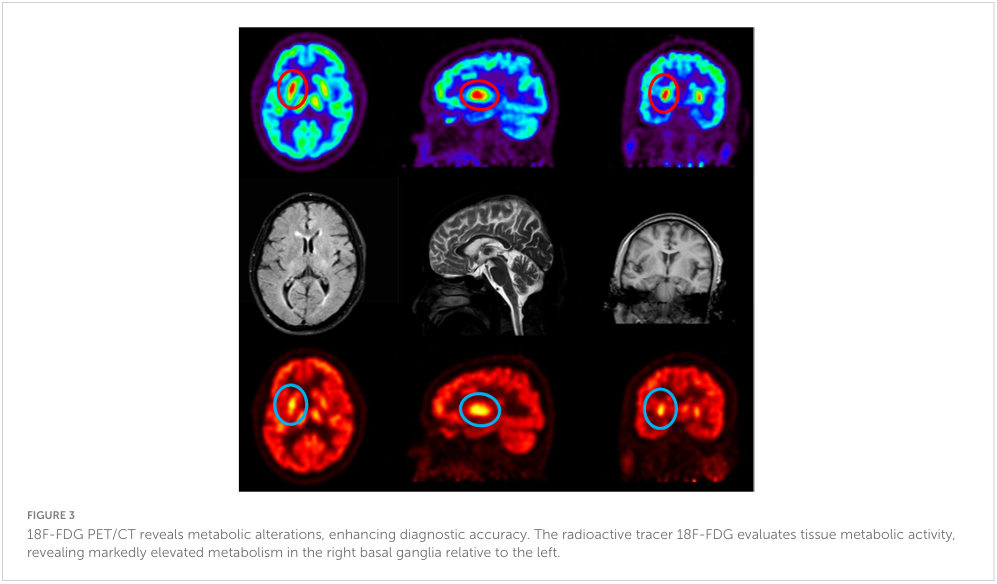

이후 시행한 18F-FDG PET/CT에서는 좌측보다 우측 기저핵에서 더 높은 대사활동이 확인되었다(Figure 3).

18F-FDG PET/CT에서 확인되는 창백핵(pallidum)의 과대사 소견 또한 병변 국소화에 도움이 된다 (19). 본 환자는 전형적인 혈액학적·신경학적 결손이 아니라, 5-메틸테트라하이드로폴산 축적에 따른 도파민성 조절 장애로 인한 드문 추체외로 증상인 급성 반신 무도병으로 발현하였다. 특히, 비타민 B12 근육주사 치료 후 무도양 운동이 신속히 소실된 것은, 비가역적 탈수초가 진행되기 전에 개입할 경우 신경정신학적 후유증이 가역적일 수 있음을 보여준다.